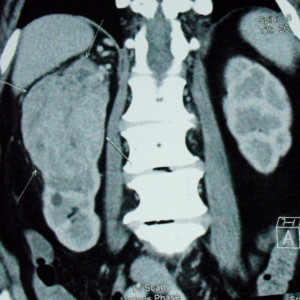

Large Kidney Tumor